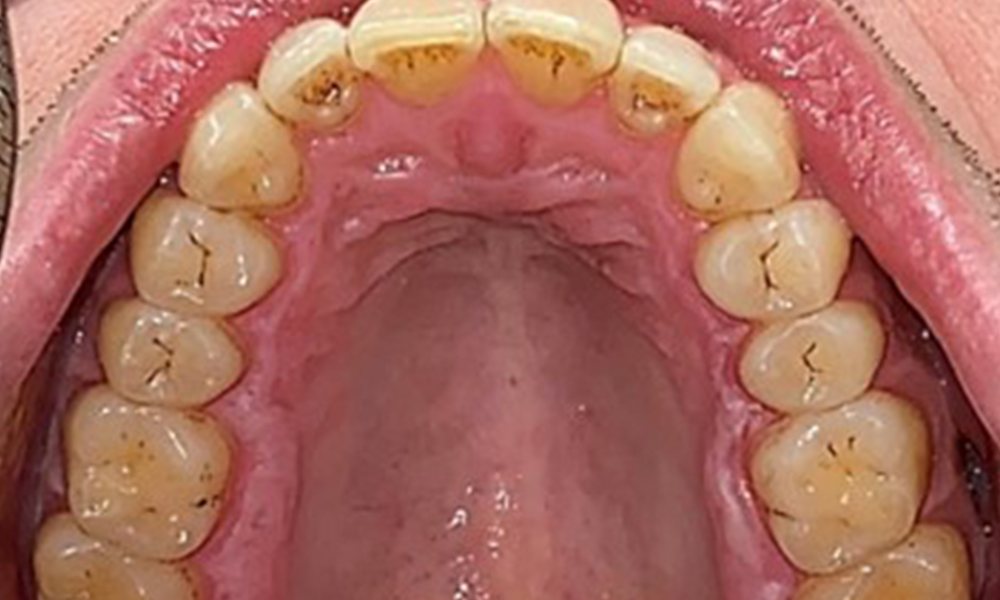

Occlusal view of the maxilla, © Dr R. Krapf

Fig. 3: Occlusal view of the maxilla, © Dr R. Krapf

There were no pathological extraoral findings. During intraoral examination, inspection of the frontal view revealed brownish discolouration near the keratinised gingiva and at the transition to the moveable mucosa (Fig. 2), which could be attributed to nicotine consumption. Whitish mucosal lesions were observed on the palate, particularly near the maxillary molar palatal surfaces, indicating increased keratinisation and can also be attributed to nicotine consumption. The tongue was covered with a removable white and brownish coating.